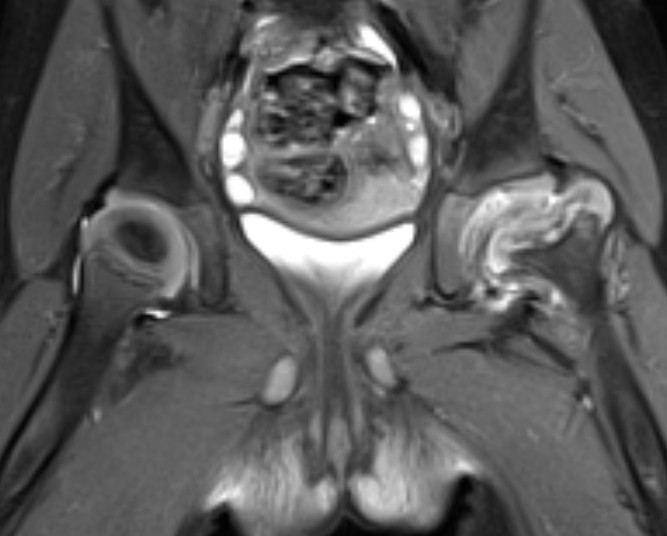

MRI

Adam et al Eur J Radiol Open 2022

- meta-analysis of MRI distinguishing between transient and septic arthitis

- bone marrow changes - 99% specific for septic arthritis

Septic arthritisSeptic arthritis

Fluid in hip joint